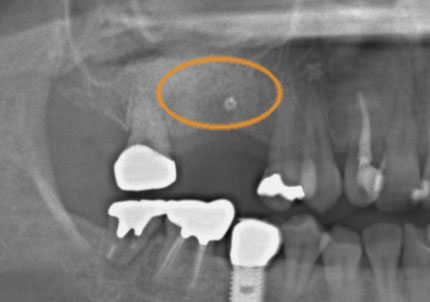

2.右側上顎洞サイナスリフト後にインプラント埋入

↑ サイナスリフト術前

↑ サイナスリフト術後

3.右上インプラント補綴物装着(2009年7月24日)

↑ 右上サイナスリフト後にインプラント埋入